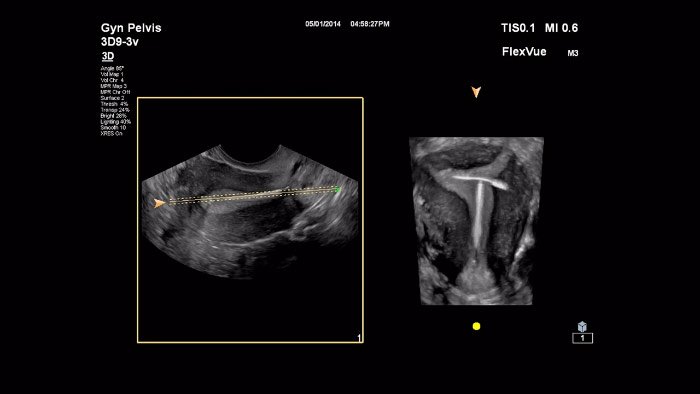

このビデオでは、Dr. Michael Rumaが当社の高度な3D評価ツールであるFlexVueについて説明しています。FlexVueでは、産婦人科病理を診断するために必要不可欠な、技術的に描出が困難な身体構造表示を、3Dボリュームにより容易に描出できます。

フィリップスには、TouchVue、MPR Touch、FlexVue、aRevealという、ワークフロー強化機能があります。これは、有益な臨床ツールである3Dワークフローをより直観的で使いやすくして、導入を促進することを目的としています。 フィリップスのTouchVueとMPR Touchを組み合わせることで、従来のものより使いやすく、直観的な3Dワークフローが実現します。システムのタッチパネル上で指を動かすだけで、ユーザーはすべての軸での3Dボリューム回転とサイズを簡単にコントロールし、すべての画面にMPRパラメータを表示できます。 ユーザーには、大きな3Dボリューム内で、必要な切断面を迅速に描出できる機能が必要です。FlexVueは、産婦人科での診断をするために必要不可欠な構造を、3Dボリュームから容易に描出できます。FlexVueは、平面に投影することで構造全体を表示できます。標準の3D編集ツールとは異なり、胎児脊椎や婦人科における子宮のように構造体が曲がっていても、FlexVueを使用して多様な直交面で全体を容易に描出できます。 当社AIUSの高度な機能であるaRevealA.I.は、関係のない3D情報を自動的に削除して、胎児の顔を迅速かつ容易に切り出します。胎児の顔の3Dデータセットを手動で編集する必要はありません。